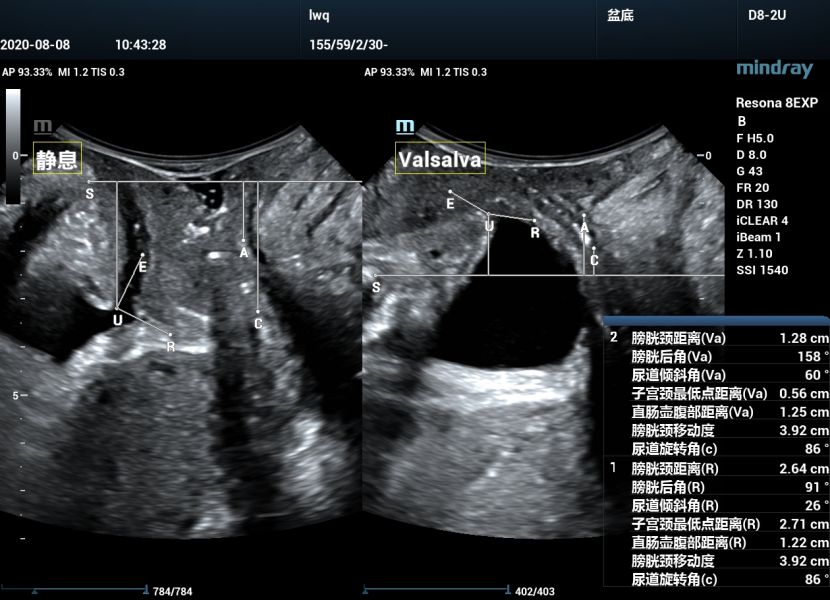

盆底二维静息状态及Valsalva动作下前中后盆腔脏器位置测量